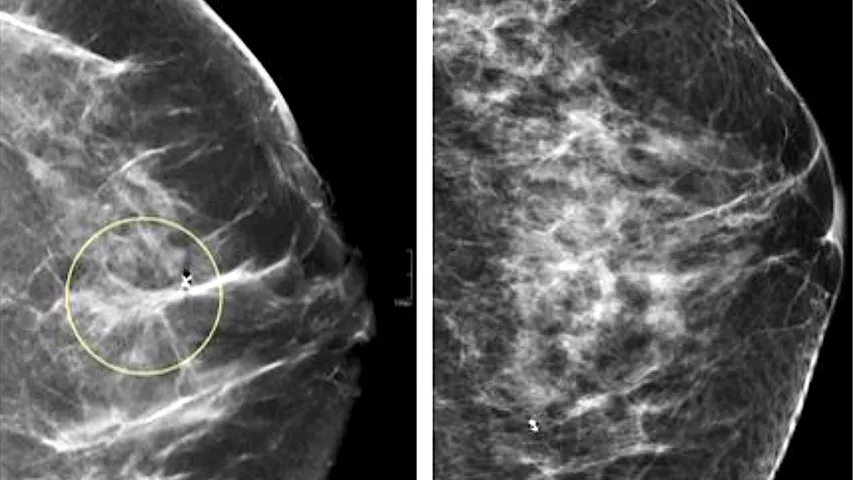

Tầm soát bằng siêu âm, nhũ ảnh (mammography) và sinh thiết giúp phát hiện sớm, nâng cao tiên lượng sống.